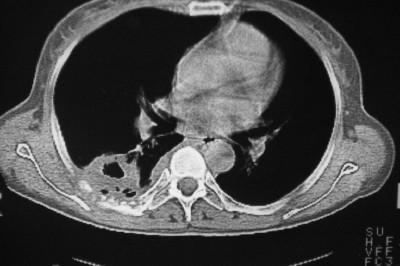

以下是引用天南地北在2007-4-10 1:49:00的发言:[br]考虑右下叶周围型肺癌伴肋骨转移。

以下是引用jone-baby在2007-4-10 8:45:00的发言:[br][br] [br] 患者[br]有发热史,x线片考虑肺脓肿.肺脓肿可以导致肋骨破坏吗?[br]脓肿可以排除吗? [br] [br] [br]

以下是引用林建春在2007-4-10 7:35:00的发言:[br]周围型肺癌侵犯肋骨

以下是引用liuyue在2007-4-10 7:56:00的发言:[br]周围型肺癌侵犯肋骨,左肺转移。

以下是引用zhangzhongshou在2007-4-10 10:24:00的发言:[br]右肺下叶背段厚壁空洞,伴胸膜改变、肋骨破坏,其内可见死骨、周围骨质硬化,左肺可见小结节影,[br]单纯影像学更支持结核。建议进一步检查。